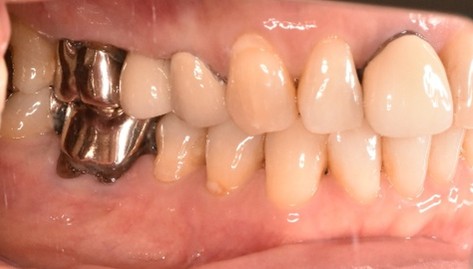

以前、1本歯がないところを、欠損の両側に被せ物をしてつないだブリッジでした。その2本のうちの前方の歯が歯根の破折を起こし、抜歯になり2本の欠損になりました。この2本の欠損を補う方法には、部分入れ歯、再度ブリッジ、インプラントの3つの方法があります。部分入れ歯もブリッジも欠損部分の負担をほかの歯に負わせるため、支台になった歯は負担が大きくなり、虫歯、歯周病、歯根破折の危険性が高まり、さらに歯を失うことになります。インプラントは、それ自身が単体で植立しているため他の歯に負担を負わすことがありませんので、咬合を回復させるだけではなく、他の歯を守る役割もあります。今回もX-Guideを使った埋入で、安心安全に行うことできました。

インプラント2本:¥363,000×2本=¥726,000(税込)

Before

After